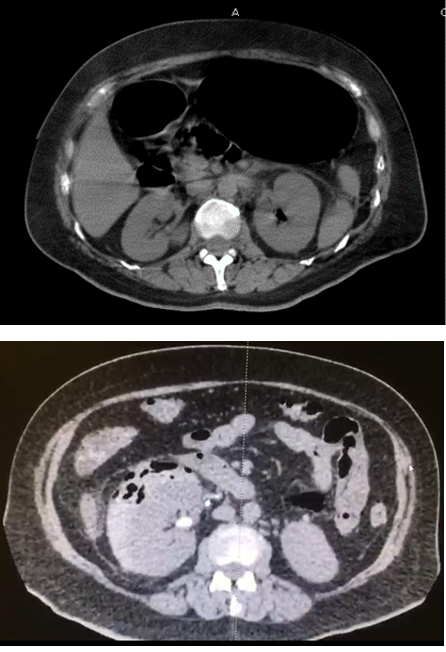

| Huang y Tseng. (1, 2) | Tomografía computada | 1. Gas en el sistema colector. (Imagen 2) |

| 2. Gas únicamente en el parénquima renal. (Imagen 2) | ||

Imagen 2 a) Huang 1.- Presencia de gas en sistema colector de riñón izquierdo. B) Huang 2.- Presencia de gas en parénquima renal.